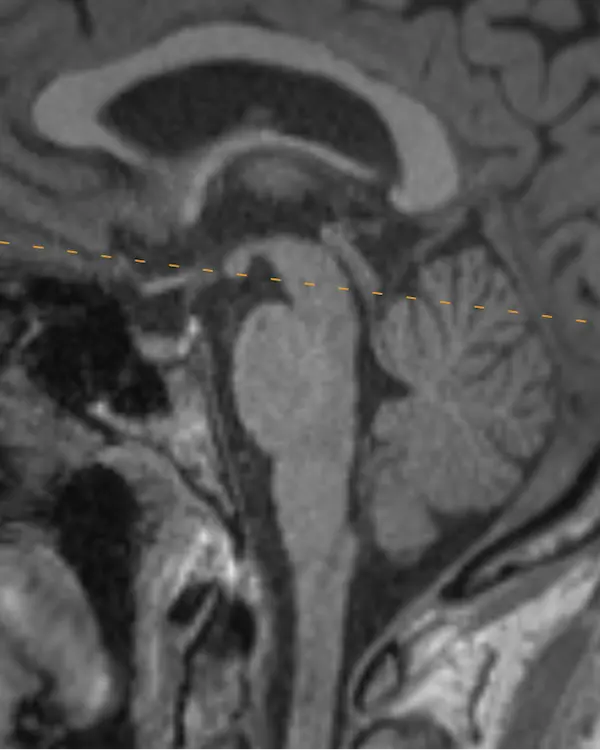

Note that axial planes in brain imaging are not perfectly perpendicular to the brainstem, they are instead created by drawing a line through the anterior commissure (AC) and posterior commissure (PC); the so-called AC-PC line. Keep this in mind when correlating the appearance of structures in the axial plane to sagittal.

The brainstem, outlined in a white dotted line, is divided into the midbrain, pons, and medulla. Each segment has a characteristic appearance that is easiest to recognize in the sagittal plane.

Notice the beak-shaped anterior margin of the midbrain and the cerebrospinal fluid (CSF) space underneath it.

The pons has a bulbous contour anteriorly and a triangular shaped CSF space posterior to it.

The medulla is thin, gradually blends in appearance with the cervical spinal cord, and has a small CSF channel posterior to it.